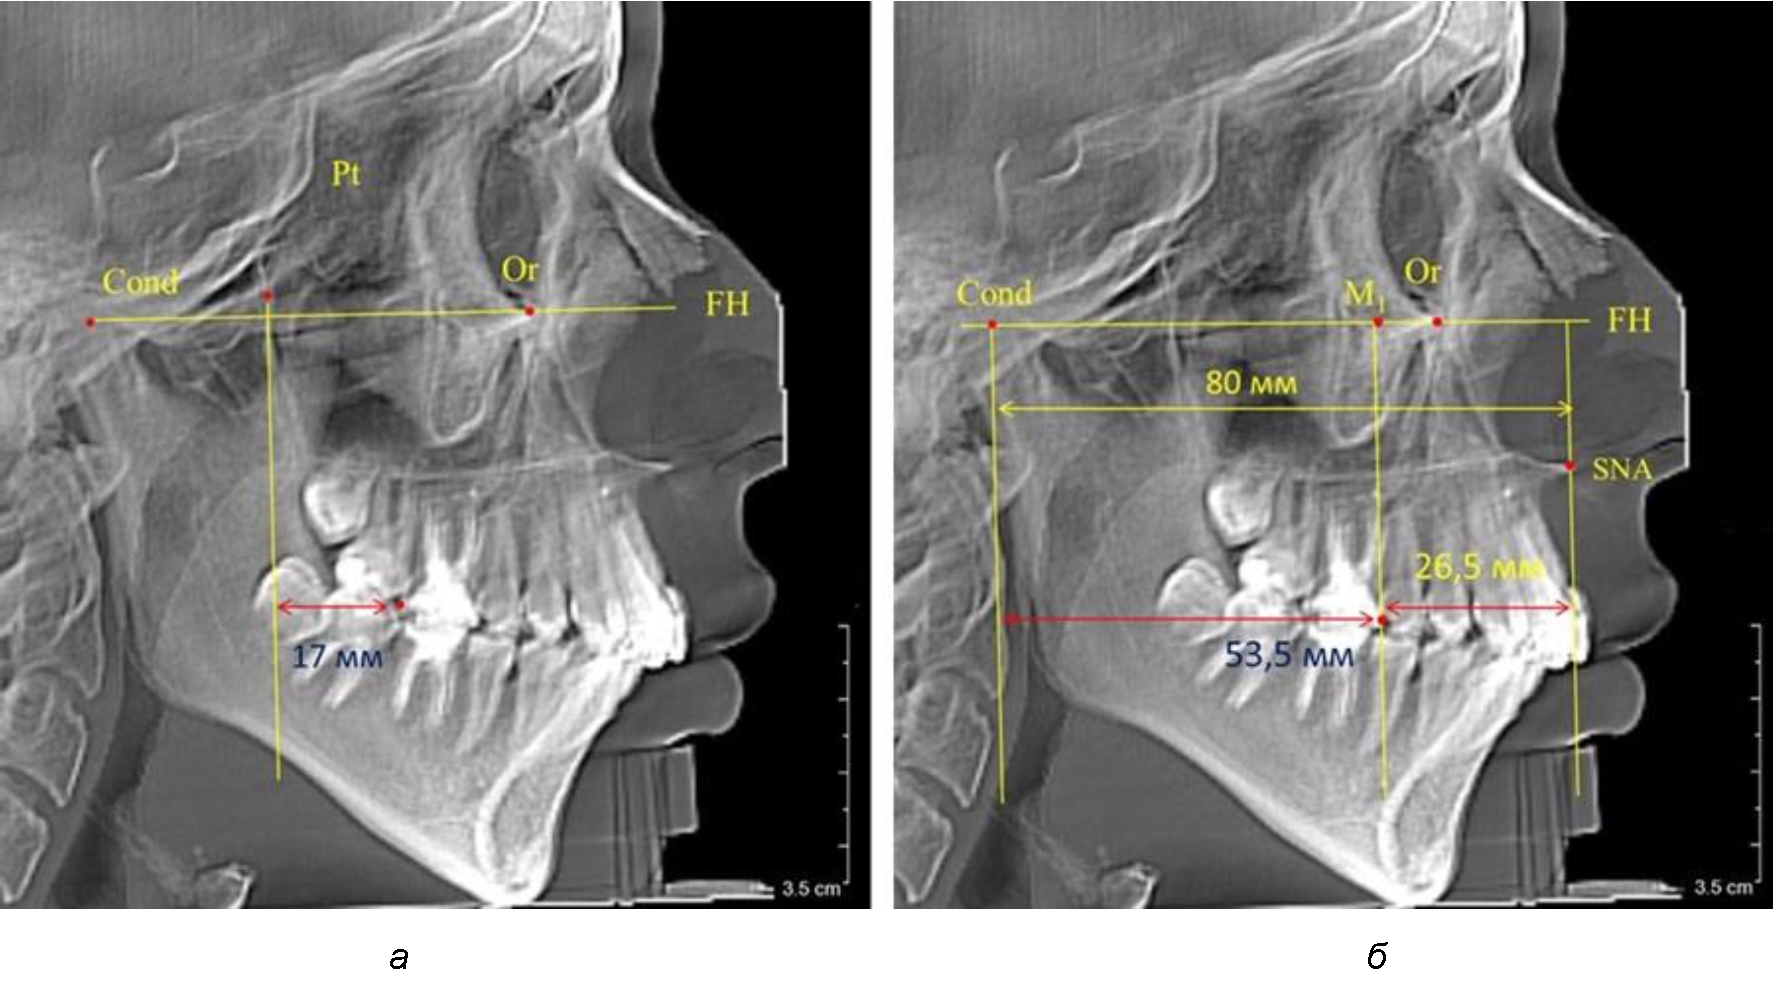

Так, при расстоянии от крыловидной вертикальной плоскости PTV до дистальной поверхности верхнего первого постоянного моляра в 13 мм сагиттальный размер гнатического отдела был 82 мм. При этом отношение кондилярно-спинального расстояния к кондилярно-молярному размеру (54,5) было близким к коэффициенту 1,5, что представлено на рис. 2.

Рис. 2. Особенности положения первых моляров по R. E. McDonald (а) и по предложенному методу (б) при уменьшенном молярно-крыловидном расстоянии